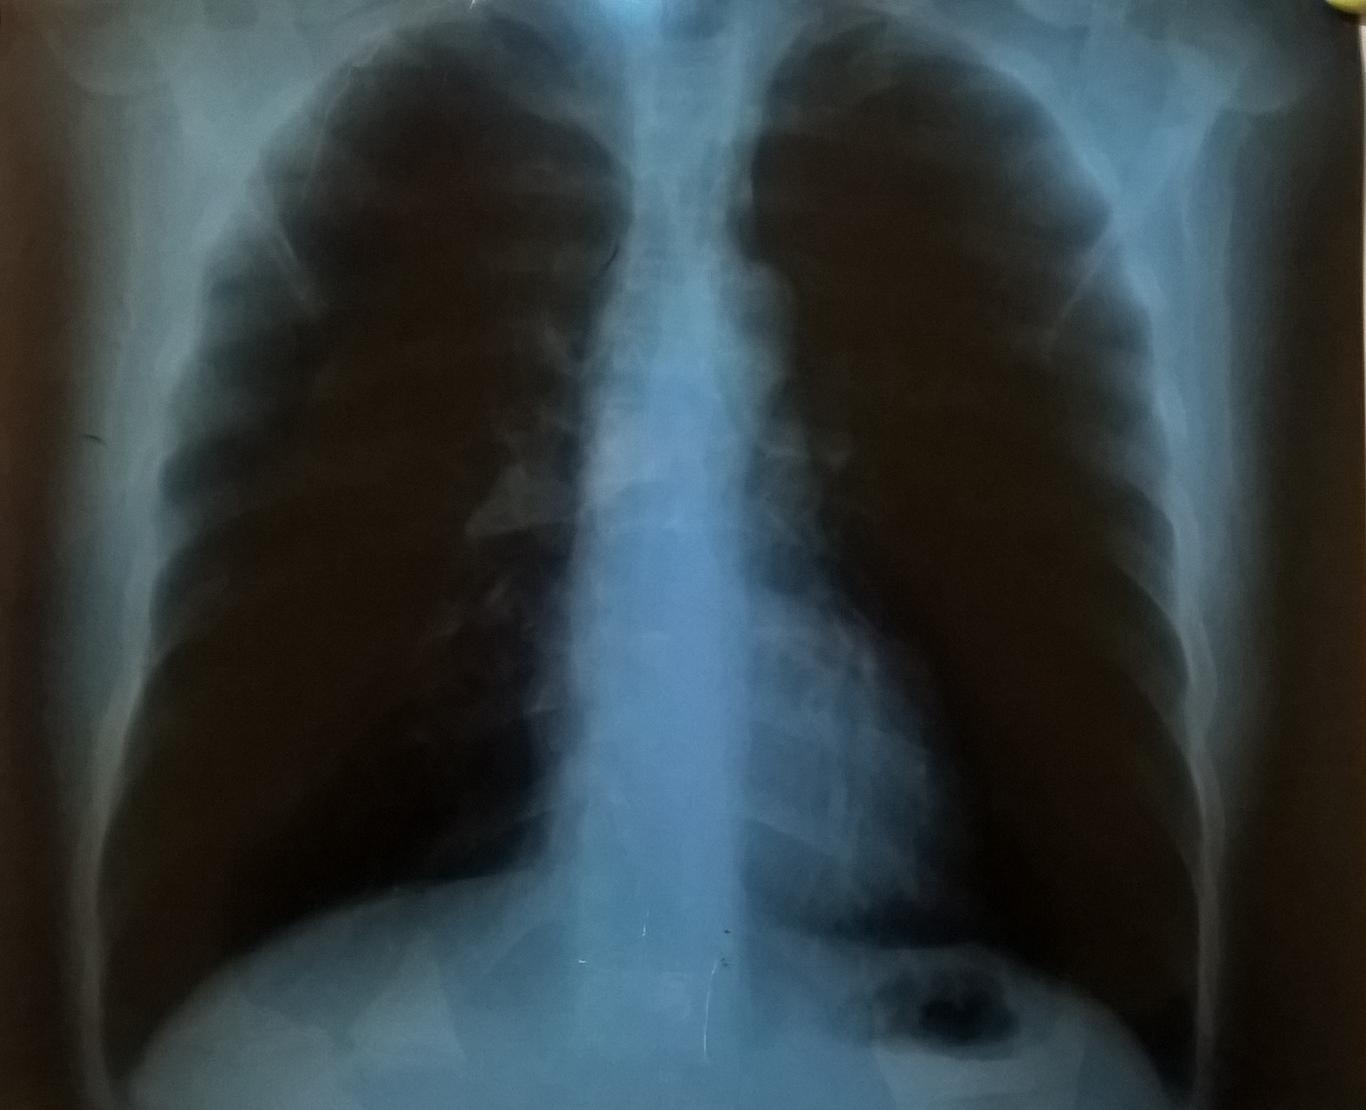

Які заходи вживають для контролю над захворюваністю на туберкульоз? Як держава може полегшити страждання невиліковно хворих пацієнтів? Чому експертна спільнота і родини людей, що живуть з наркозалежністю, виступають за лібералізацію наркополітики в Україні? Як захистити своє право на отримання якісної медичної допомоги? Відповіді на ці та інші питання вже скоро ви почуєте на Громадському радіо.